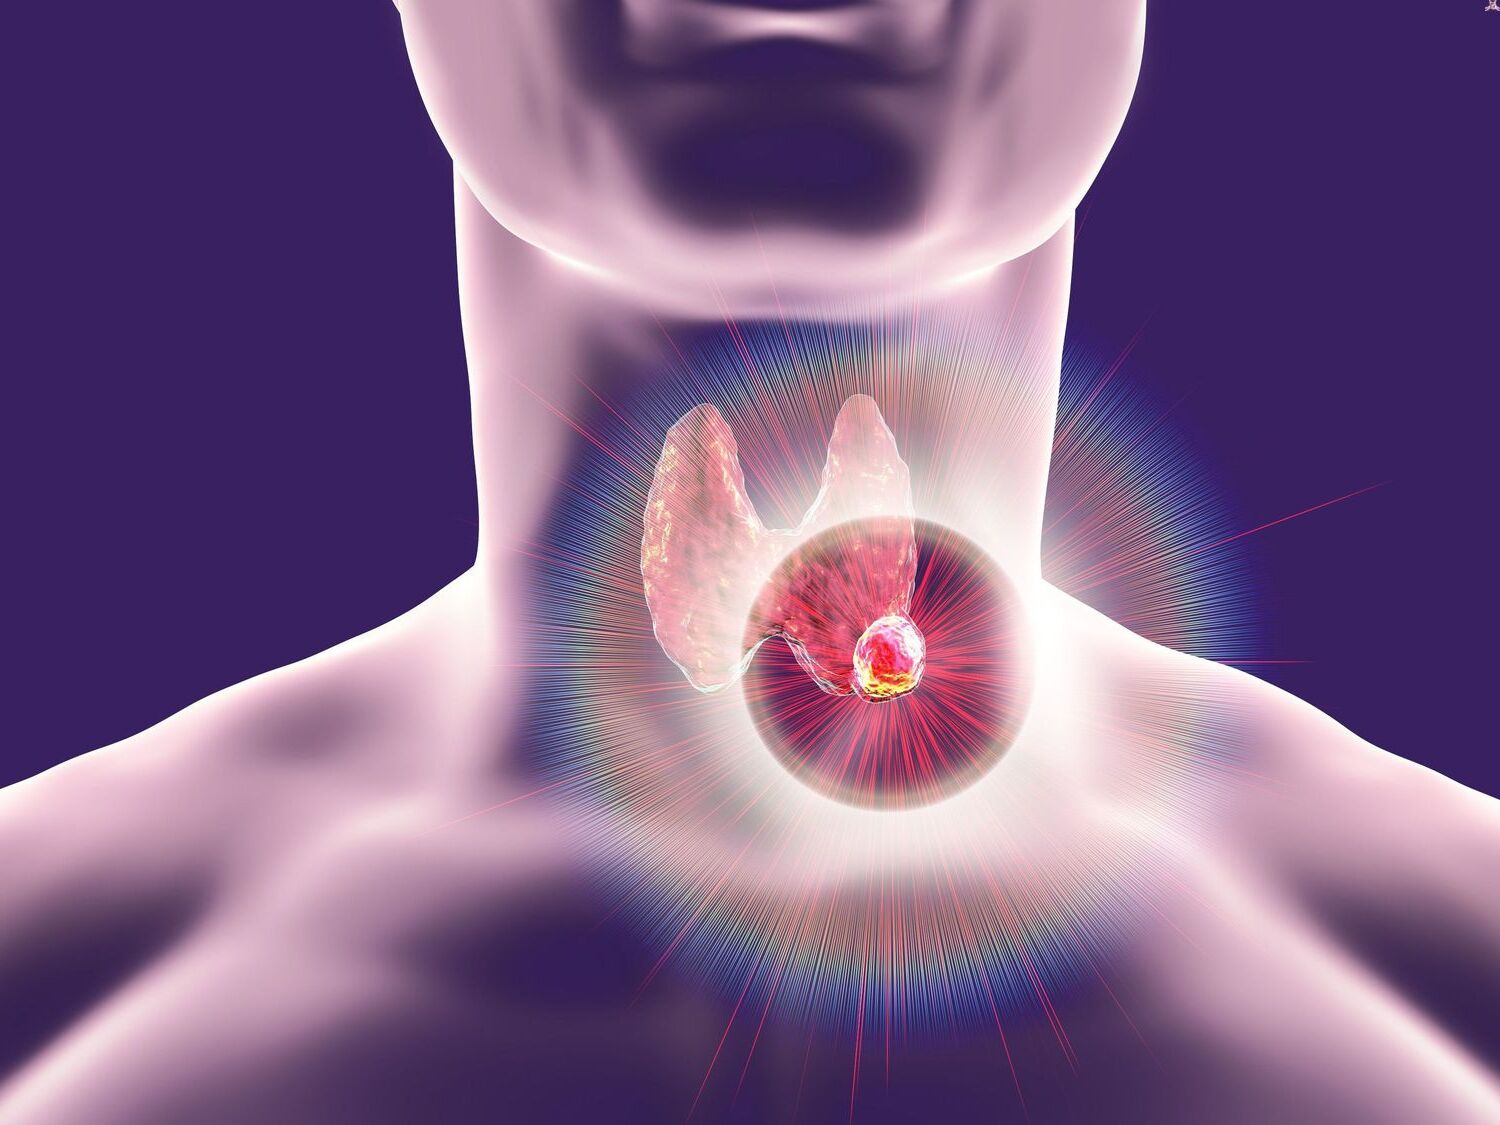

20 Best Facts About Thyroid Cancer Facts

https://facts.net/wp-content/uploads/2024/06/20-best-facts-about-thyroid-cancer-1718817819.jpg